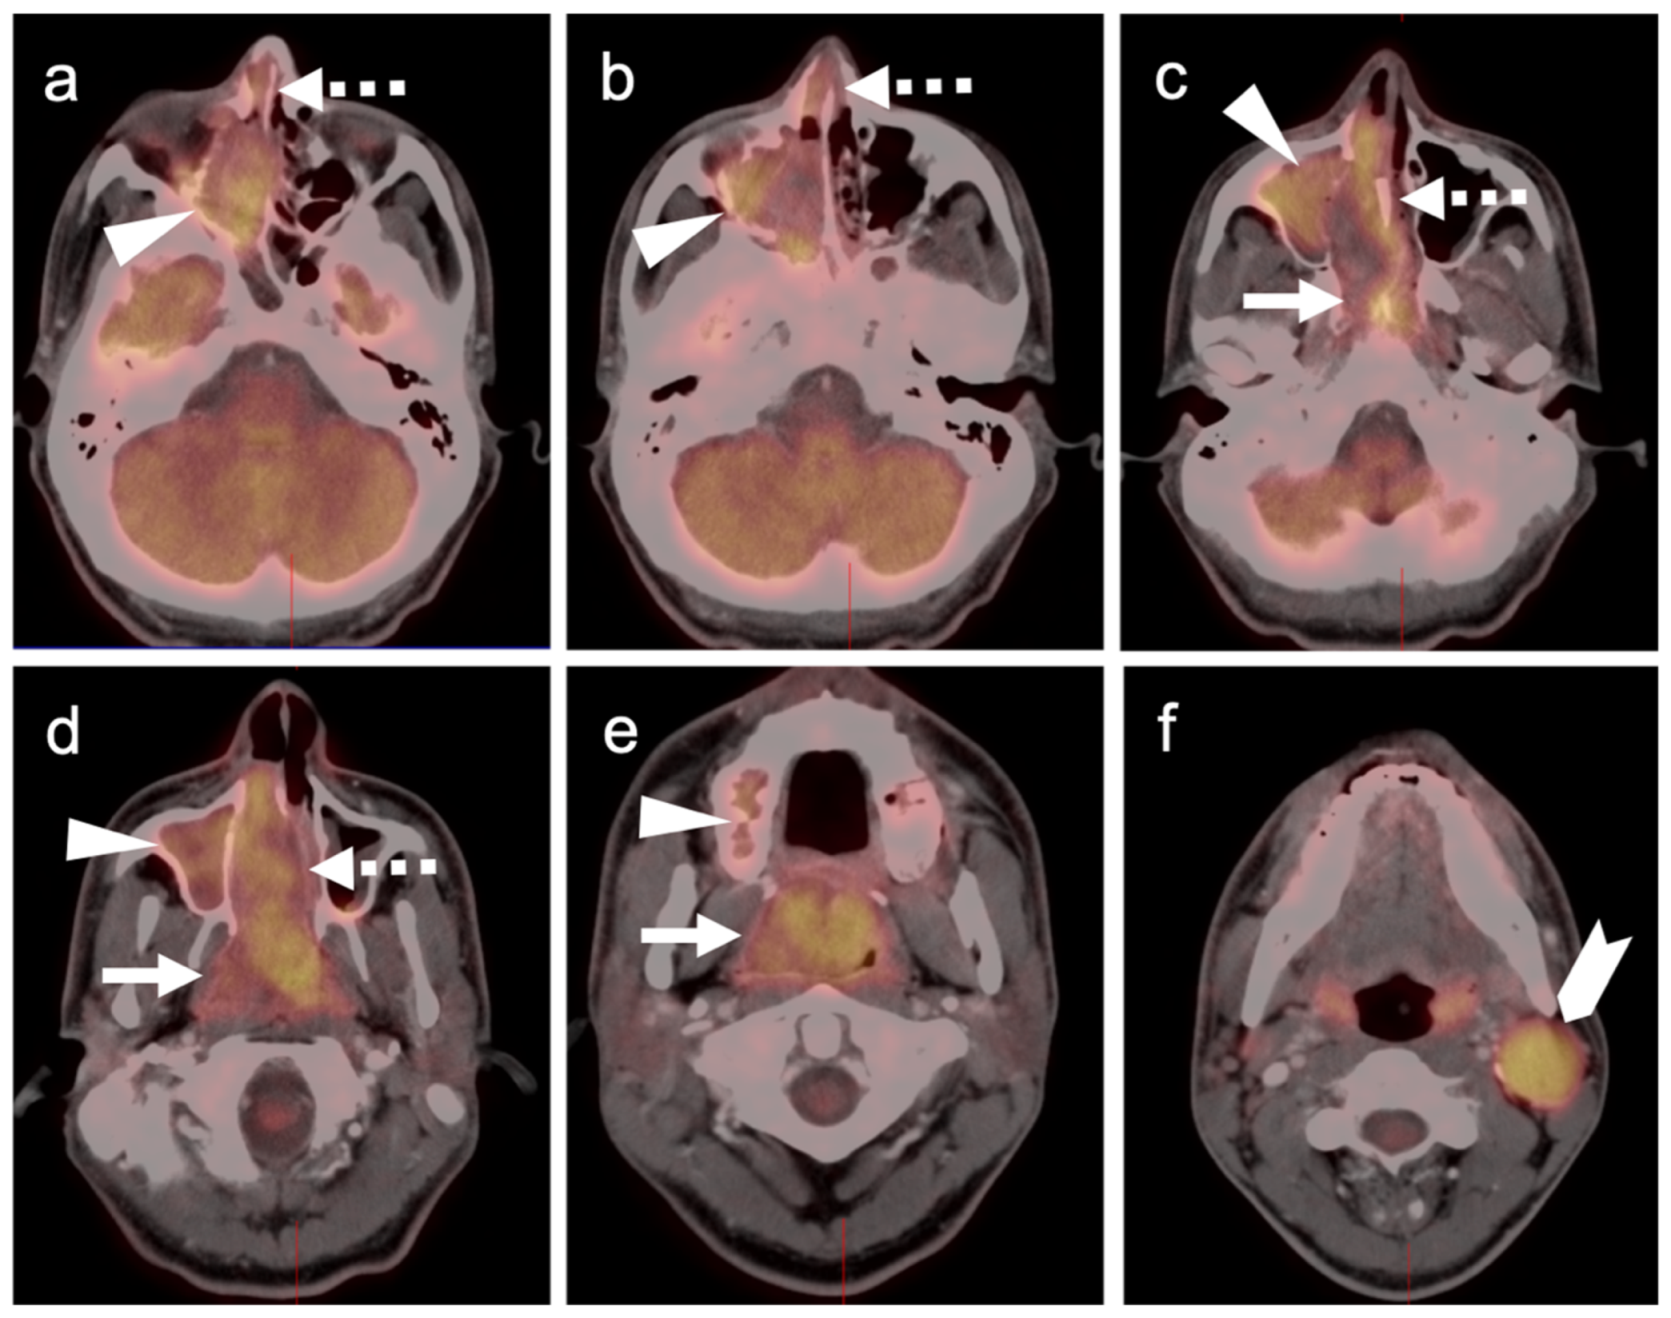

4.5. Pheochromocytoma and Paraganglioma